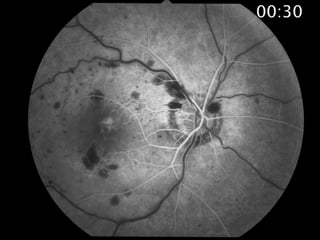

Venous occlusion Arterial hypertension Retinaltelangiectasia Macroaneurysm Retinal tumor Cystoid Epiretinal gliosis Uveitis Retinitis pigmentosa Diabetic retinopathy Retina Other vaso-occlusive diseases Vasoocclusive retinal disease Diabetic retinopathy Arterial hypertension Macroaneurysm Nonyper Irradiation cystoid uorescence Tumor eakage Inflammation Photocoagulation Detachment of sensory retina Choroid Detachment of pigment epithelium New-formed blood vessels Inflammation to the uvea, retinal and optic nerve hea Vitreous Tumors of the retina and of the optic nerve head Physiologic Vascular occlusion Drusen Optic pit Coloboma Optic Nerve Scar Choked disc Papilledema Inflammatory changes